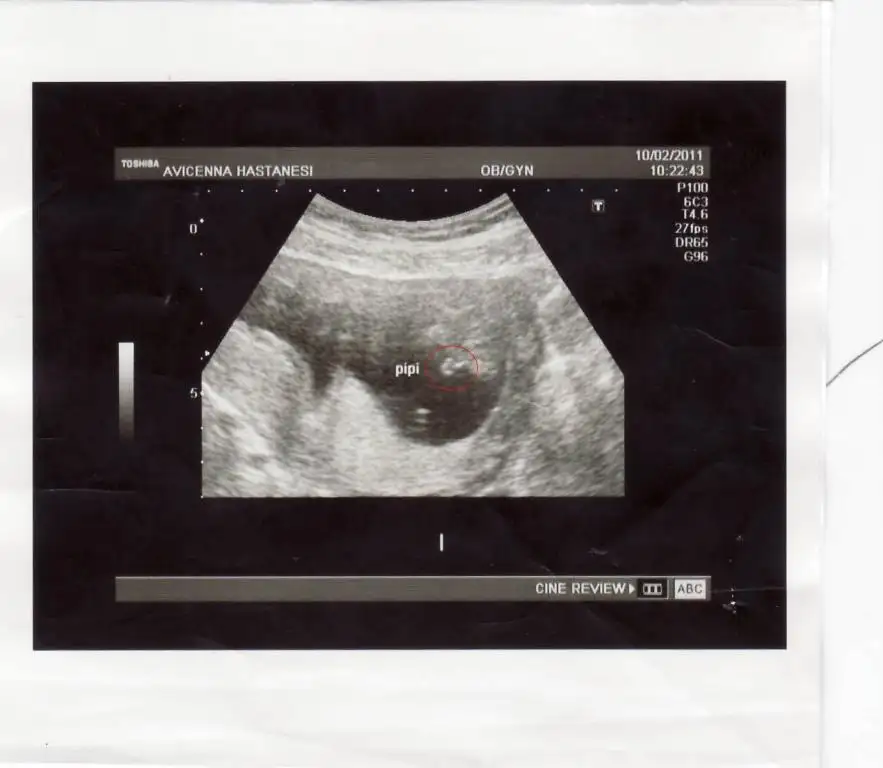

Eki Görüntüle 142791

bacaklarını açmıştı oğlum doktor teyzeside böyle çekti işte

kırmızı yuvarlak içine aldım